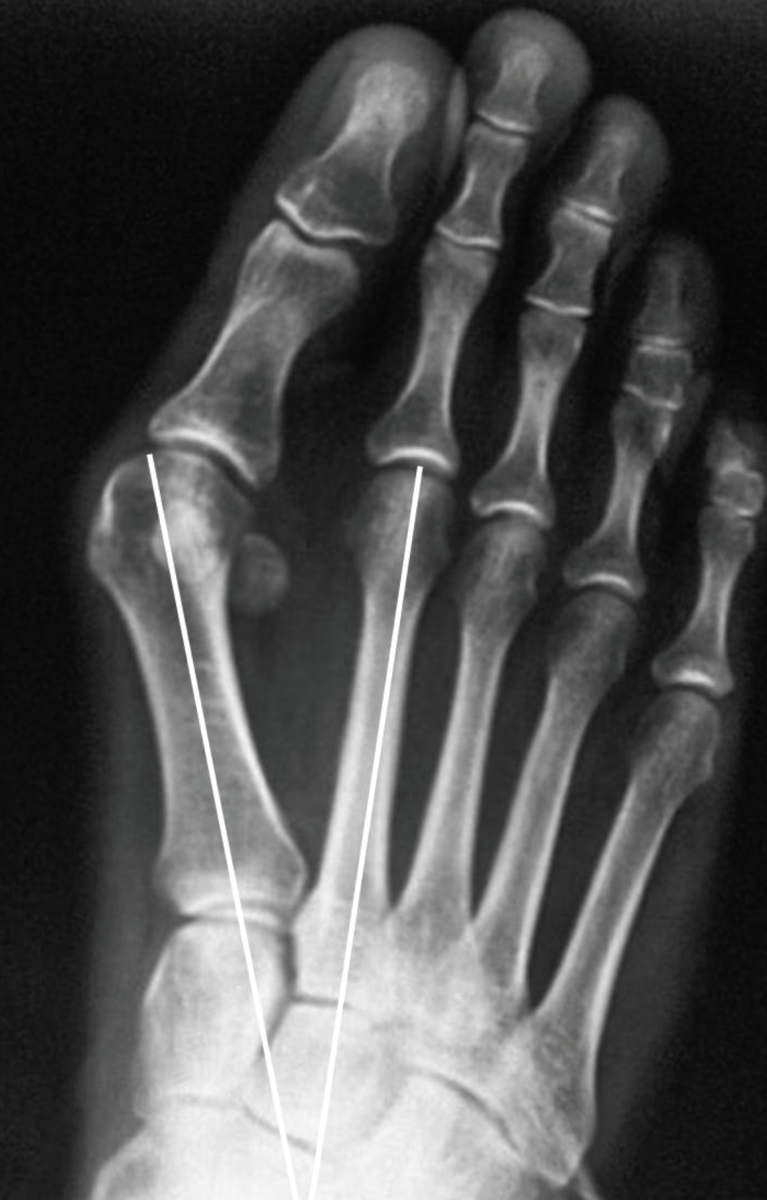

Halluks valgus grafisi. Birinci ve ikinci tarak kemikleri arası açılmış. Birinci tarak kemiği içe doğru kaymış.